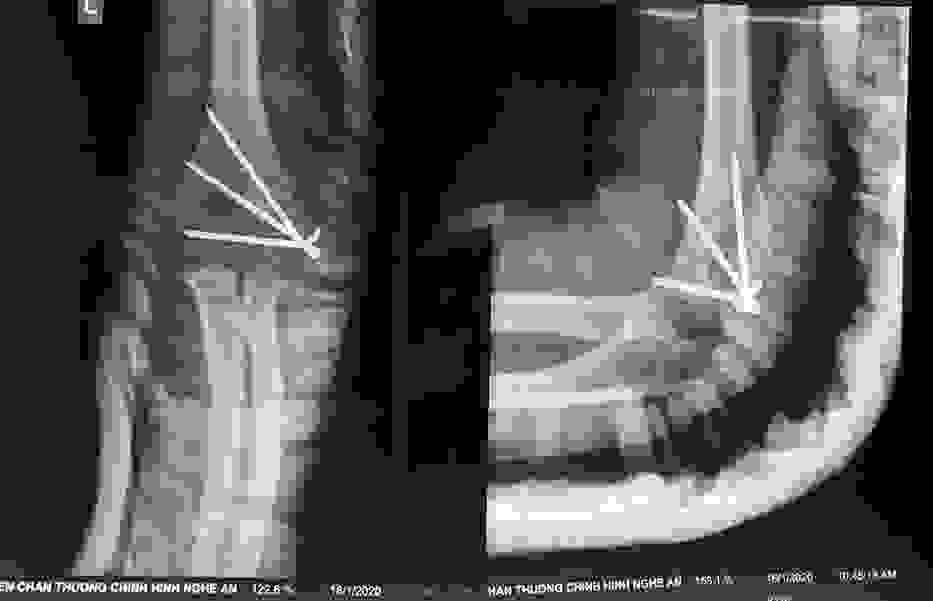

Phẫu thuật thành công ca bệnh hiếm gặp...khớp giả bẩm sinh xương chày

26/06/2019 17:00

Đã xem: 3380

Bệnh viện Chấn thương- Chỉnh hình Nghệ An, vừa phẫu thuật thành công cho bệnh nhi khớp giả bẩm sinh xương chày